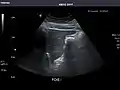

Gallbladder

Gallbladder: No stones, wall thickening, or pericholecystic fluid.

Common Bile Duct: Nondilated measuring 1.3 mm at the level of the porta hepatis.